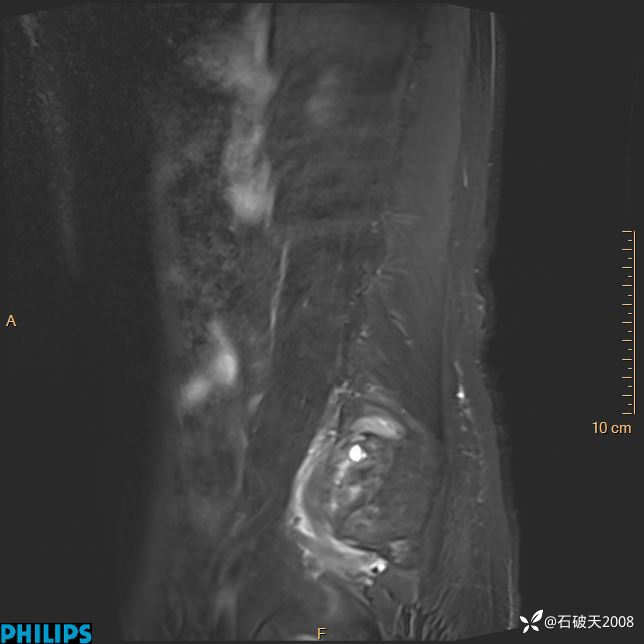

2023年3月份MRI影像

ADC